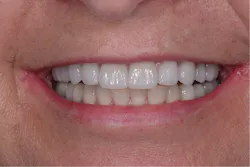

Figure 8: Anterior smile view of the patient’s final restoration